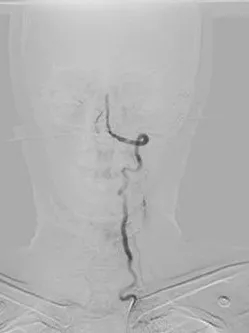

導(dǎo)管順利到位后造影顯示患者為右側(cè)椎動(dòng)脈顱內(nèi)段纖細(xì),基底動(dòng)脈中上段閉塞。施宏飛副主任醫(yī)師與介入團(tuán)隊(duì)尹志強(qiáng)醫(yī)師用微導(dǎo)管及導(dǎo)絲配合,小心地一點(diǎn)點(diǎn)通過閉塞的血栓,快速而細(xì)致地進(jìn)行著每一步操作,每一分鐘、每一秒鐘對于患者都至關(guān)重要。閉塞的血管早開通一分鐘甚至都會(huì)多挽救出更多的腦組織。

術(shù)前